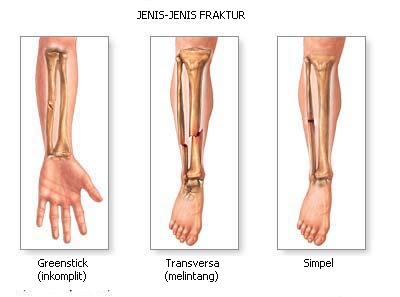

Jenis Dan Kategori Tulang Patah

Jenis Dan Kategori Tulang Patah